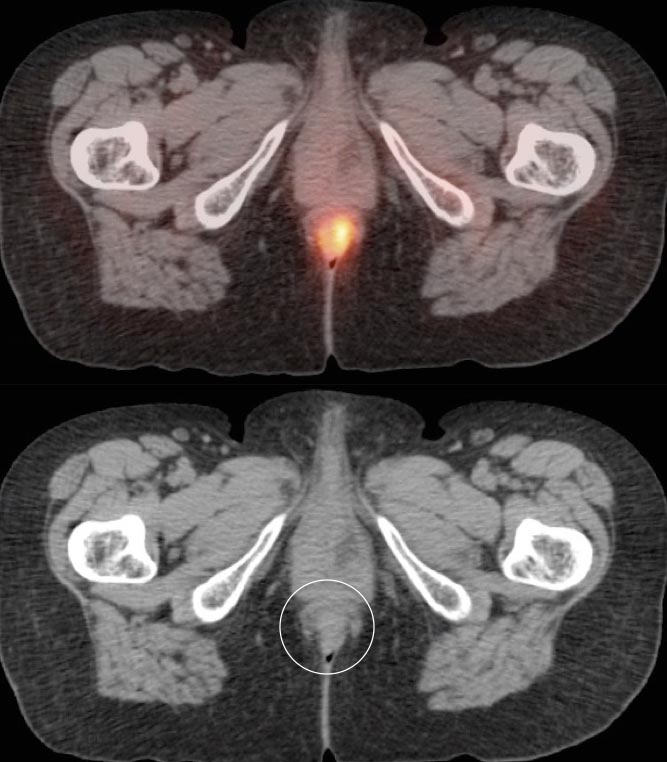

Focal intense uptake in the ano-rectal region is a very common finding. It is considered normal in the absence of an associated soft tissue abnormality. It is often attributed to hemorrhoidal inflammation.

Be careful to not confuse ano-rectal uptake (typically representing hemorrhoidal inflammation) with rectal uptake (often malignancy).